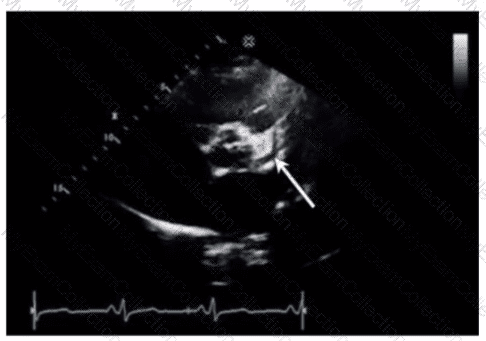

An intravenous drug user presents with a fever of unknown origin, flu-like symptoms, dyspnea, and chest pain. Which ultrasound finding is mostly likely associated with this presentation?